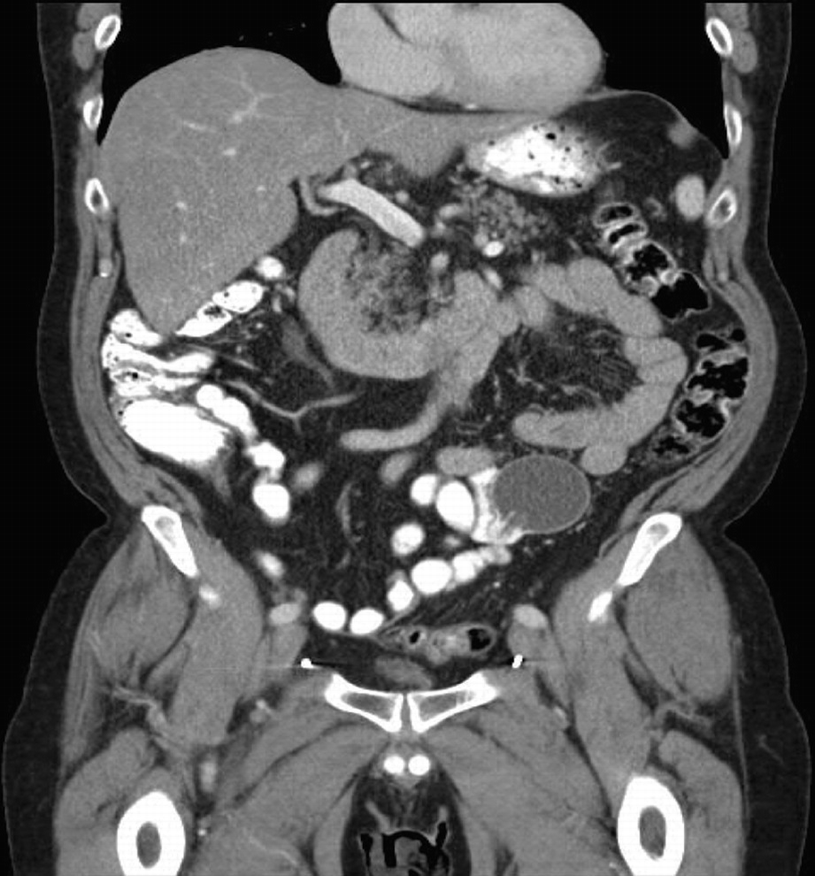

Pre-operative CT scan demonstrating intra-peritoneal IPP reservoir

New onset urinary symptoms after IPP warrants evaluation with urinalysis, pressure-flow study, post void residual, and cystoscopy to rule out erosion. Cystoscopy usually demonstrates external compression of the bladder due to the reservoir, particularly in patients with large cylinders that require a larger volume reservoir. This is of no consequence to a knowledgeable implanter unless the surface of reservoir is visible. This distortion may also be noted on CT imaging where the bladder is displaced medially due to a large reservoir. CT should not be considered as a substitute for a cystoscopy to rule out erosion. Additional considerations include external compression by the exit tubing or pump relative to the urethra in cases of obstructive urinary complaints.